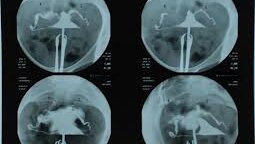

Важно! ГСГ (Гистеросальпингография)

Пожалуйста, не отказывайтесь! Уважаемые представительницы прекрасного пола, эта статья скорее для вас, чем для мужчин. Но и многим мужчинам важно знать, как важна эта процедура, когда планируется беременность, когда семья планирует ребенка. 16 февраля у меня был день траура- это число однажды было роковым для меня- в этот день у меня была операция- внематочная беременность. Я этого ребенка ждала больше всего на свете! И тем числом потеряла его. Раннее мы с мужем решились на этот важный шаг - родить ребенка...